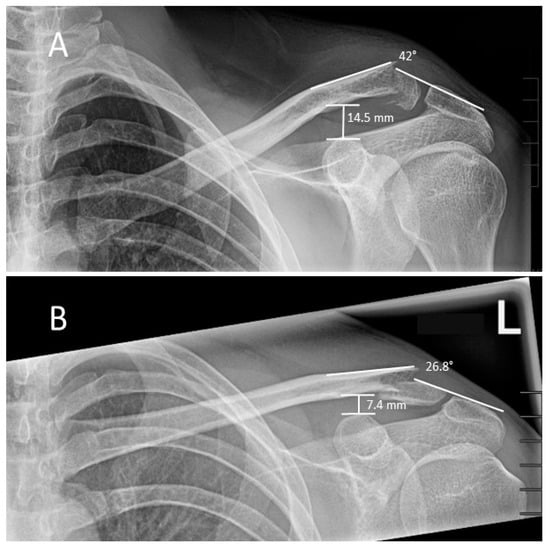

Additionally, the authors evaluated the angle of the fracture fragments relative to each other in Neer I and Craig IIc fractures. Figure 4 shows two examples of Neer I versus Craig IIc fracture fragment angles. For evaluation, in the anterior-posterior view, a line was drawn across the proximal portion of the clavicle, from the ligamental insertion area to the fracture. A second line was drawn across the acromion and distal clavicle parts. The mean angle in Neer I fractures was 25.1 ± 3.3° versus 36.8 ± 4.4° in Craig IIc fractures (p = 0.02).

Figure 4. Evaluation method of the fracture angles and CCD in a.p.-X-rays. (A) 38-year-old male with Craig IIc fracture. The CCD was 14.5 mm, and the fracture angle was 42°. (B) 30-year-old male with Neer I fracture. The CCD was 7.4 mm, and the fracture angle was 26.8°.

Despite these results, the authors believe that cross-sectional imaging is not necessary as the gold standard. As observed in acromioclavicular-joint injuries, the regular coracoclavicular distance (CCD) is between 11–13 mm and there should be no greater than 5 mm difference between both sides in anterior-posterior view [17,18]. Additionally, the difference in the fracture angles of Neer I and Craig IIc fractures was indeed significant and might be a tool for distinguishing these fracture types. Although the collective was too small to be reliable, larger case series are required to define a cut-off angle. However, at present, an angle of >30° can be assumed approximately as a parameter of instability.